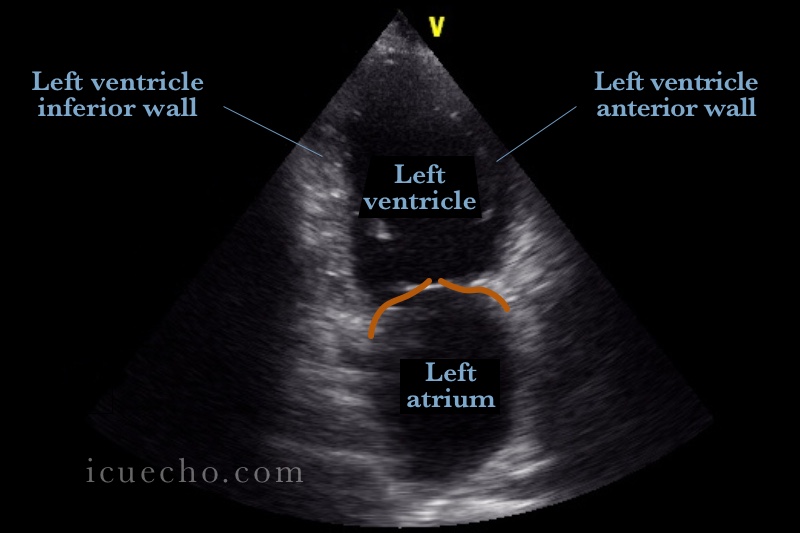

From icuecho.com

Apical 2 Chamber ICU & Echo Apical Dyskinesis Although wall thickening of most lv segments can be assessed by. On physical exam, lv apical dyskinesis may be detected as systolic apical displacement during palpation. Assessment of wall motion of the left ventricular (lv) apex by transthoracic echocardiography (tte) is problematic as it is. This is the first study evaluating this novel diagnostic measure for detecting lv apical dyskinesis.. Apical Dyskinesis.